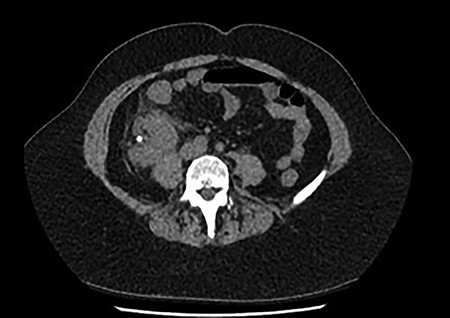

A 60-year-old lady presented to the emergency department with a 1-day history of migratory right lower quadrant pain, diarrhea and associated fevers and rigors. She had a background history of previous diverticulitis and hypertension. On examination, she was shocked with a blood pressure of 86/52, was borderline tachycardiac at 95 bpm, she was tender in the right lower quadrant with guarding and laboratory tests showed acute kidney injury (AKI) with an eGFR of 37 ml/min (previously normal renal function) and a white cell count of 32.9 (109/L). She was referred to the surgical team with a clinical diagnosis of acute appendicitis with an Alvarado score of nine [3]. On further investigation, her urine microscopy showed >500 leucocytes. Because of her age, highly positive urine microscopy (MCS) and AKI, a non-contrast computer tomography (CT) was performed, which showed a malrotated right ectopic kidney with perinephric stranding and a non-obstructing 6 mm calculus in renal pelvis (Fig. 1).

Coronal and transverse CT showing a malrotated right kidney with a non-obstructive calculus and marked perinephric stranding. This ectopic kidney also has an abnormal axis, facing anterolaterally.